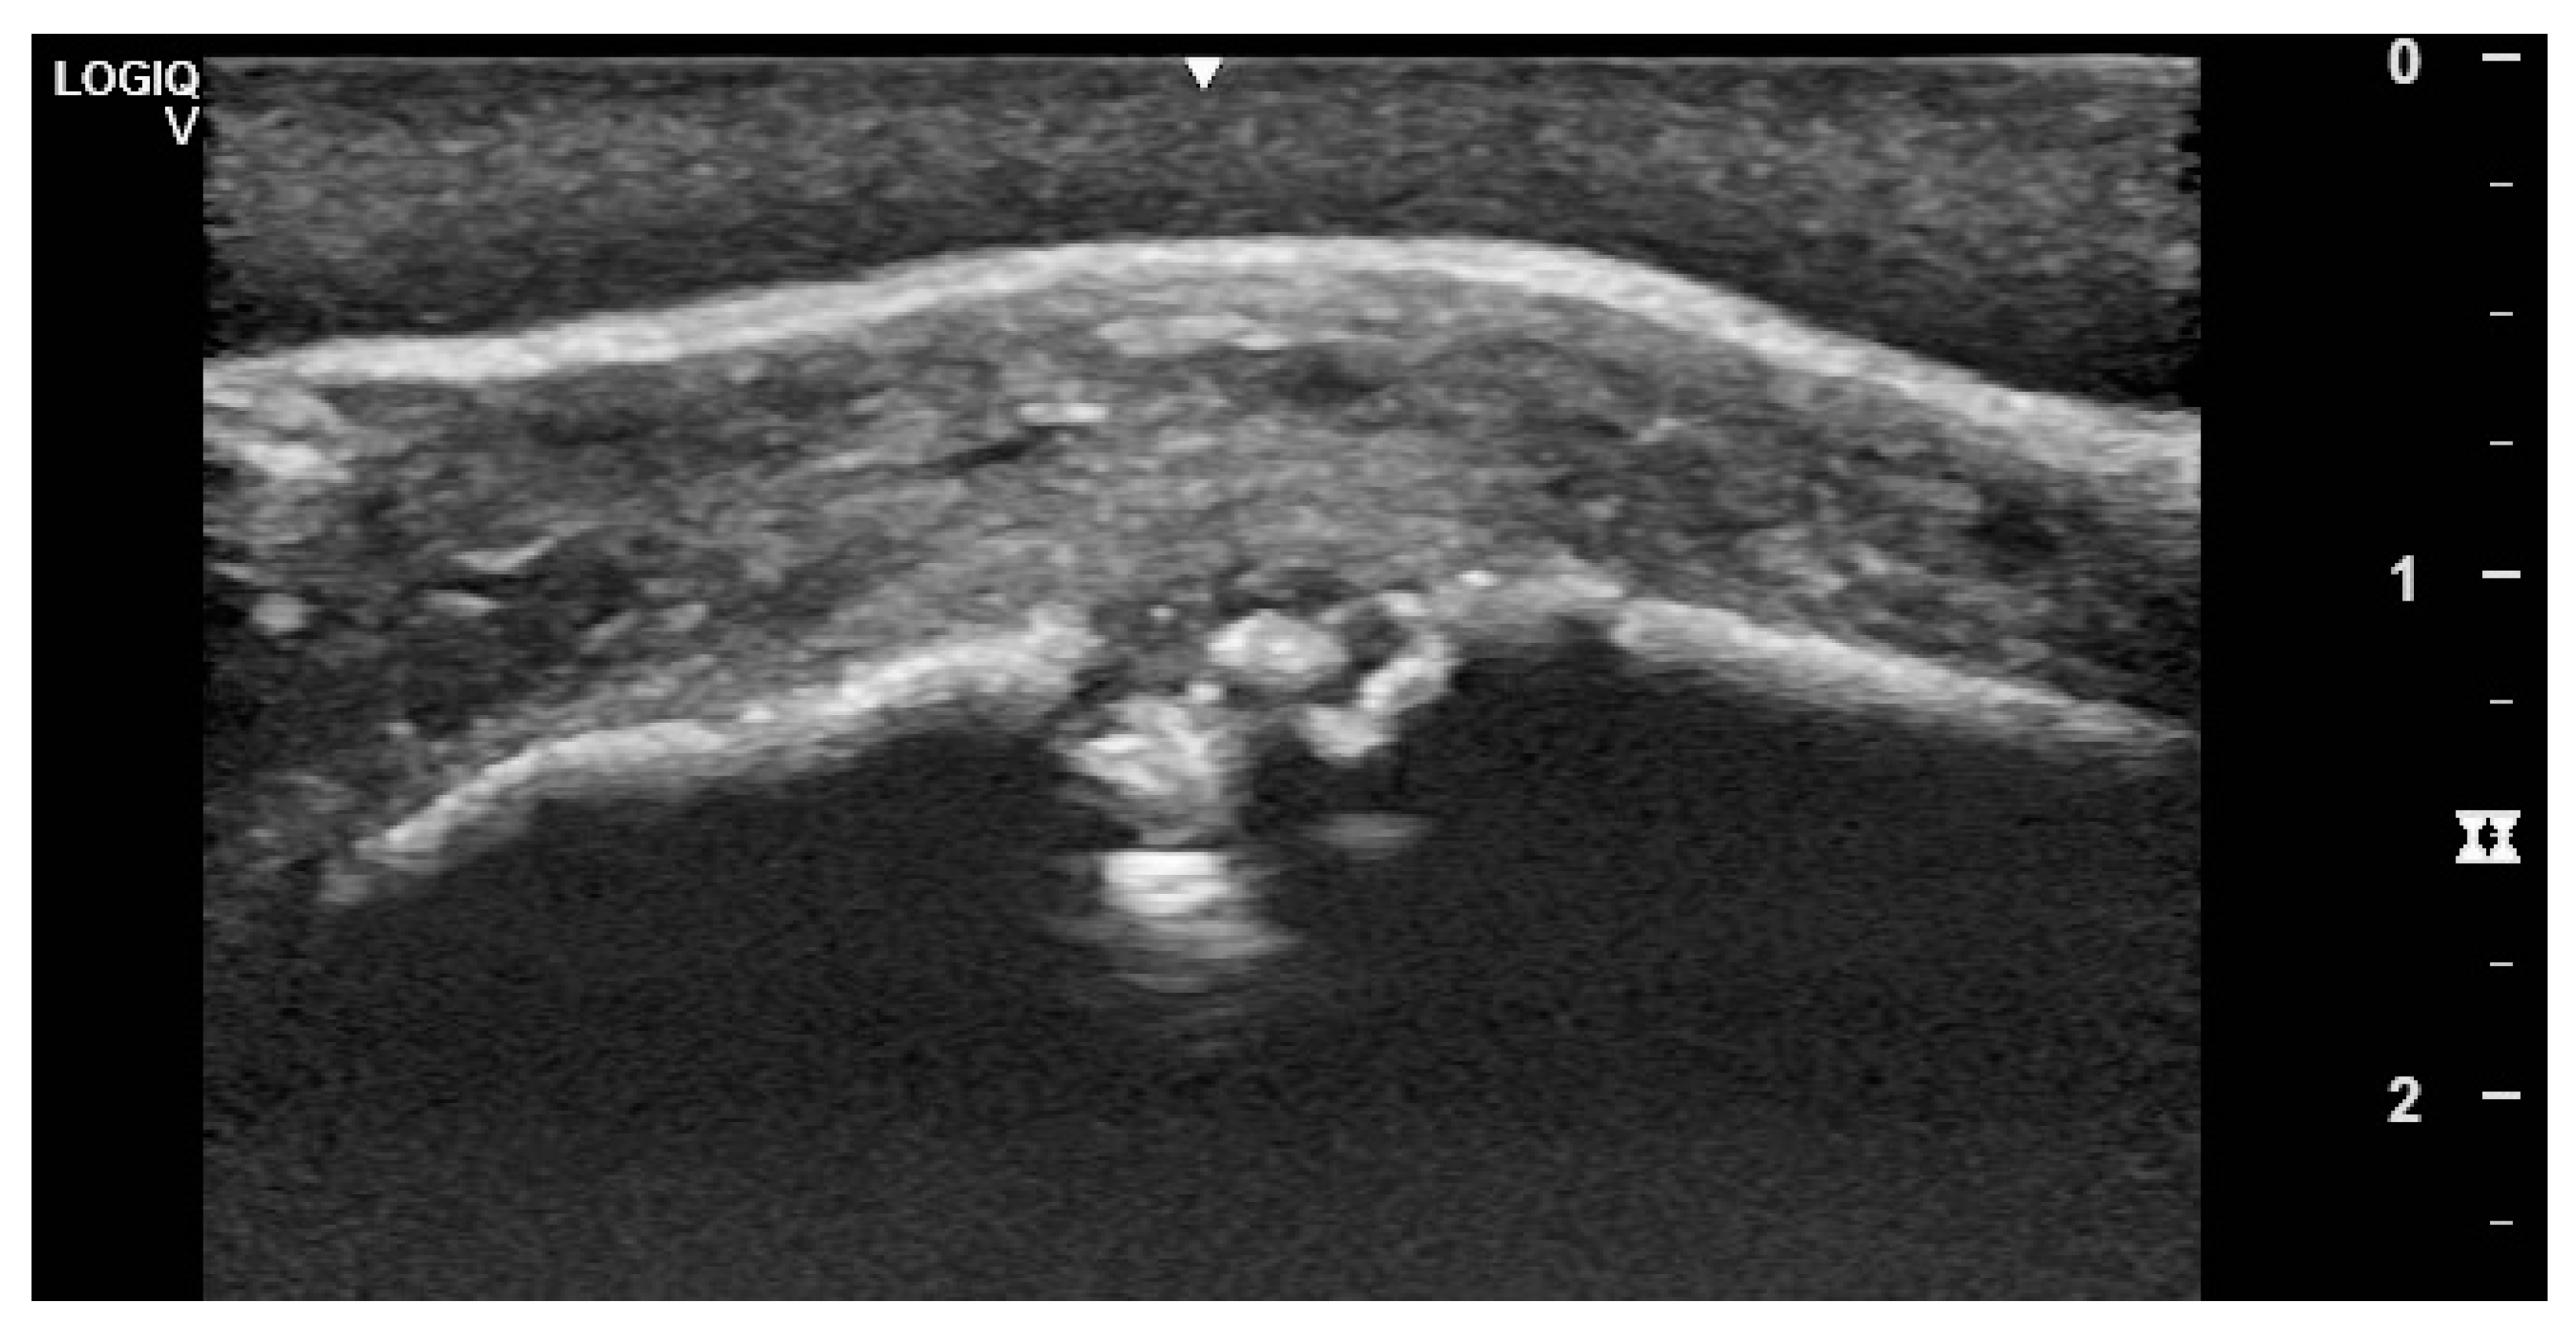

3.2. Imaging Findings